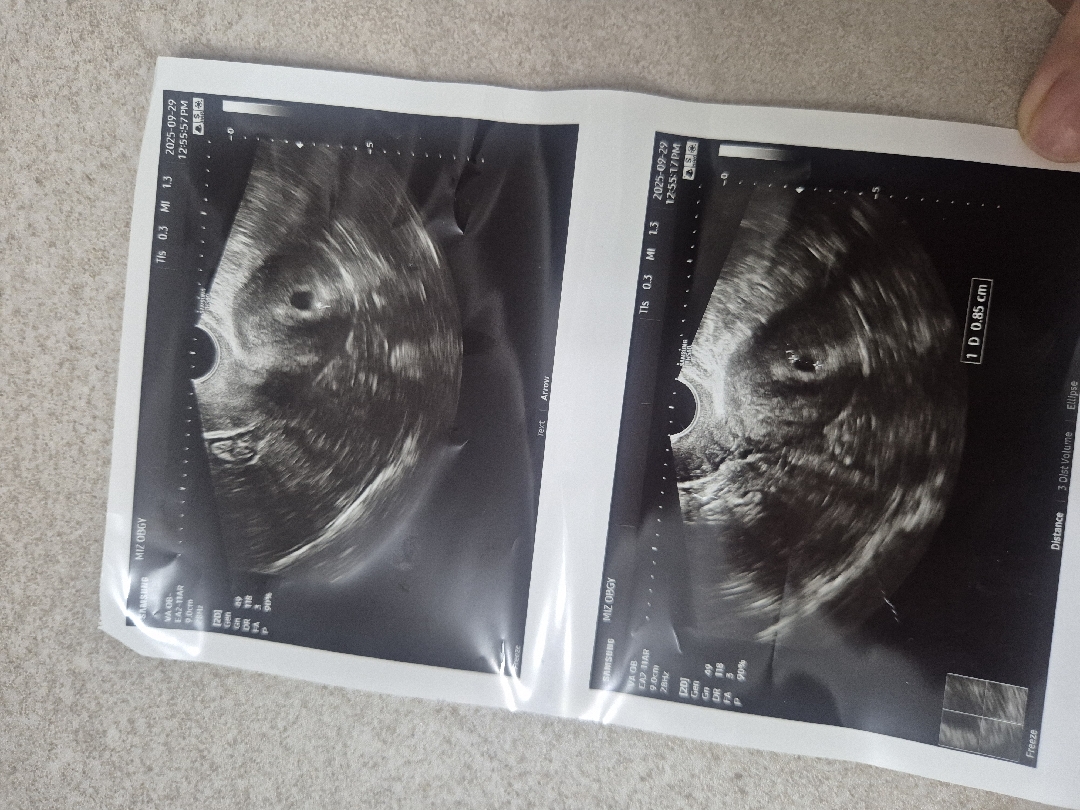

난황은 언제보알까여ㅠ

월요일에 아기집맠 보고왓구 담주토요일에 진료가는대 이번주도 초음파보러가고싶어 미치겟어용... 월욜에 5주0일차쯤이라고하셧는데 아기집 위치나 크기는 괜찮은거겟죵..ㅎ